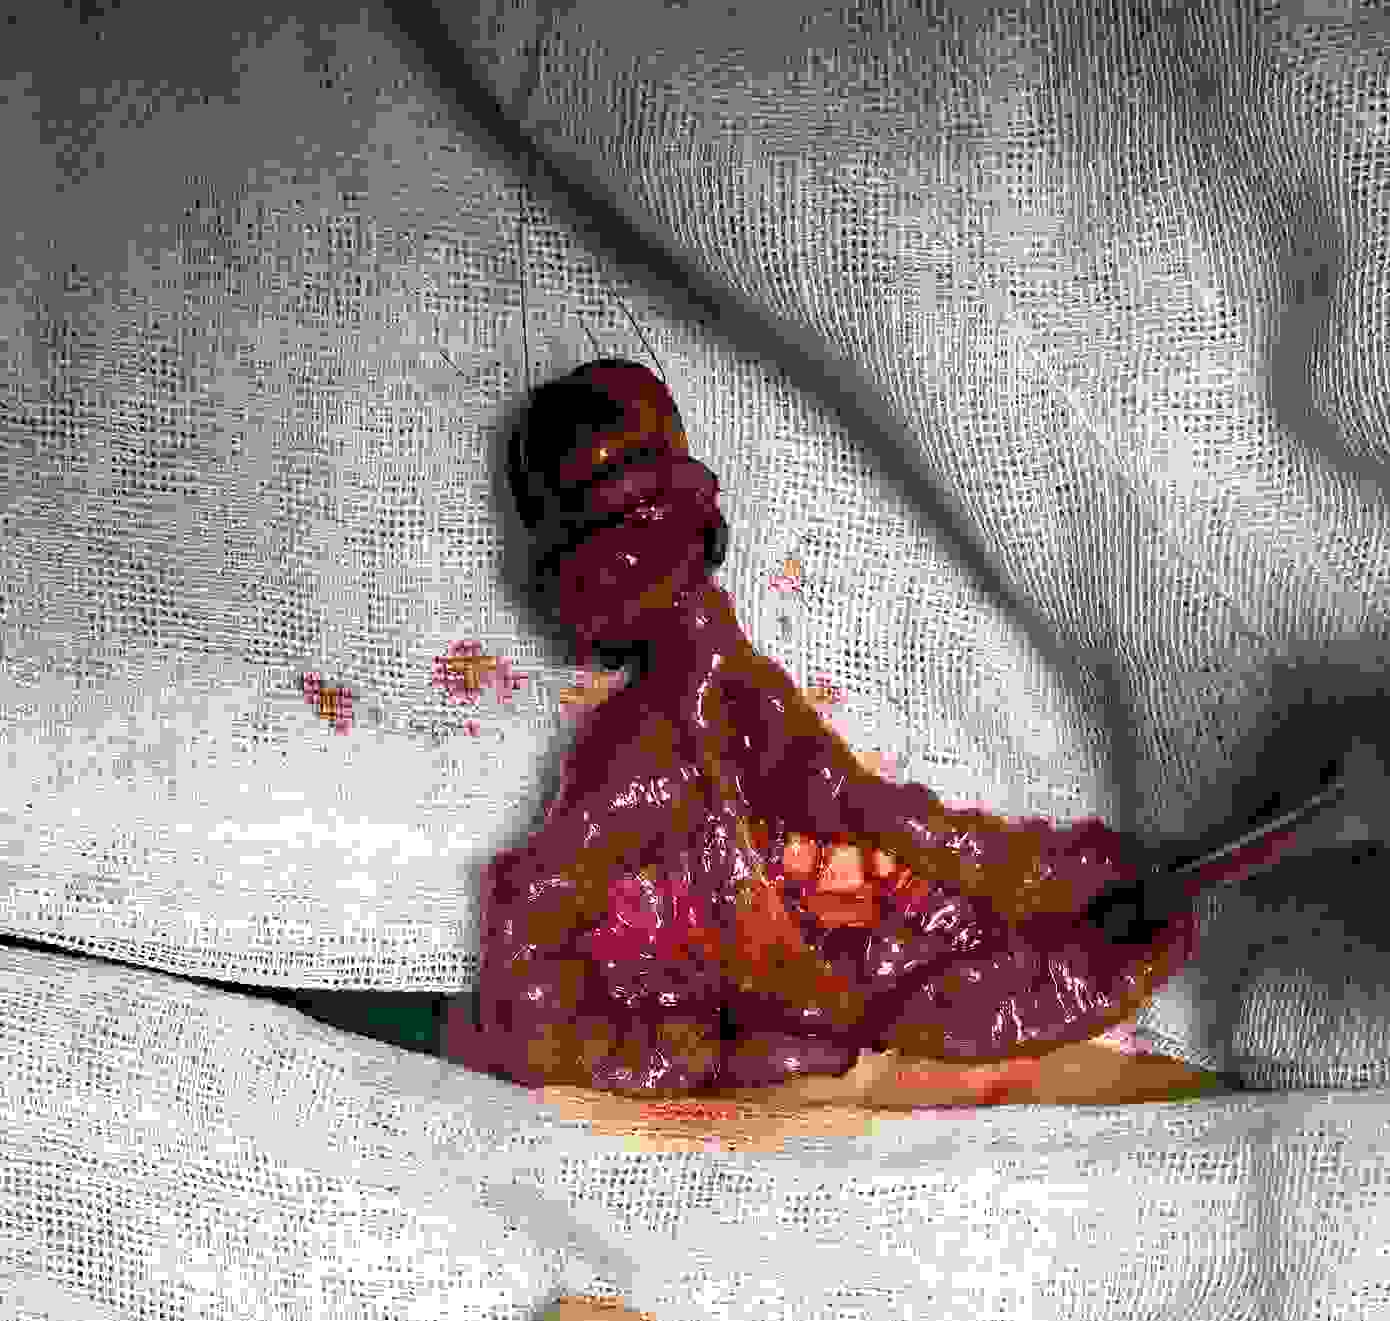

【脐肠瘘】昨日我院小儿普外新生儿外科团队,诊断并顺利完成脐肠瘘手术一例。该病有数据统计发病率为15000分之一。在我院每年出生的2万多例宝宝也是仅仅发现了这一个。该病属于卵黄管未闭。需要外科手术治疗。该病以脐部漏粪、排气为特征性表现,常见症状有间歇性渗液、腹压增加时(比如按压肚子、咳嗽)渗液增加等。若瘘口较小,可仅有脐部潮湿、局部炎症等表现;若瘘口较大,还可见脐部有红色肿物突出,这是瘘管粘膜外翻的表现。

图片发自160App图片发自160App图片发自160App图片发自160App